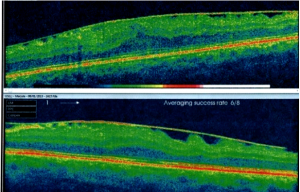

anelli intrastrominali anestesia angio oct atrofia del nervo ottico avastin cataratta Cheratocono chirurgia delle vie lacrimali chirurgia refrattiva chirurgia vitreo retinica corsoecm Dacriocistorinostomia degenerazione maculare senile edema maculare Endoscopia nasale epiretiniche Femtolaser foro maculare intervento di cataratta ipermetropia laser ad eccimeri laser a diodi Laser a femtosecondi laser argon laser yag macula malattie retiniche miopia OCT oftalmopatia tiroidea PRK ptosi palpebrale pucker pucker maculare puker maculare retina retinopatia diabetica retrazione palpebrale simposio oculistico sindrome interfaccia vitreo retinica trattamenti anti-aging trombosi venosa retinica vie lacrimali vitrectomia vitreopatia